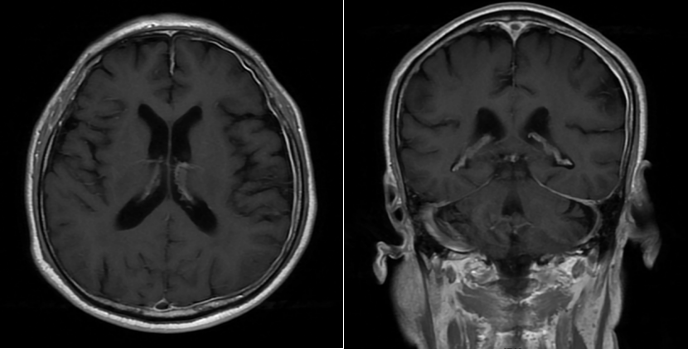

找到折磨刘先生的“元凶”后,予以激素冲击以及抗感染等治疗,刘先生的头痛很快得到明显缓解,激素递减后联合免疫抑制治疗,出院时刘先生的头痛已完全缓解。

(3月后,复查头颅增强MRI提示脑膜增厚较前好转)